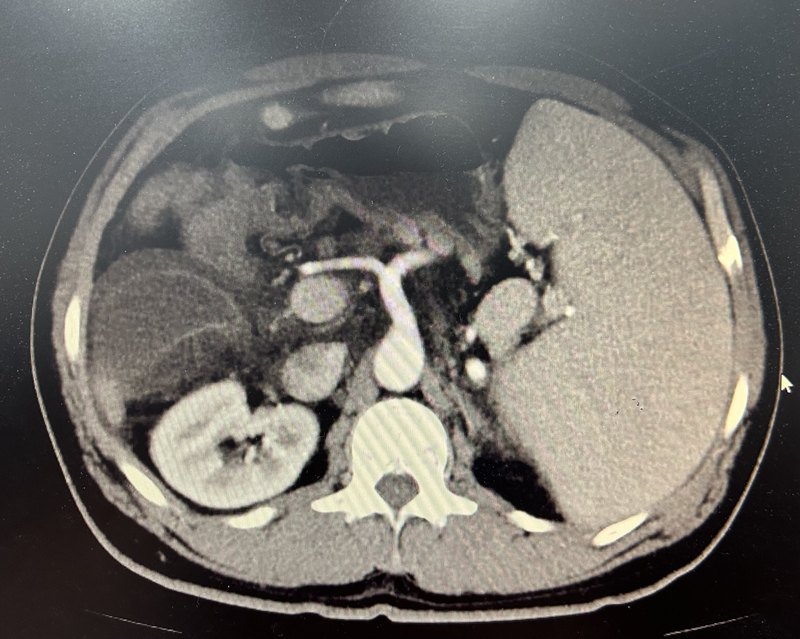

患者女性,58歲,特發(fā)性門脈高壓癥,外院檢查是胃底部粗大的曲張靜脈團(tuán)合并胃腎分流,出血風(fēng)險大,且存在內(nèi)鏡下治療禁忌?;颊咂⑴K顯著增大,白細(xì)胞、血小板顯著降低,脾功能亢進(jìn)重。輾轉(zhuǎn)就診多家醫(yī)院,未確定合適的診療方案,最后于我院住院,行脾部分切除斷流術(shù),術(shù)后恢復(fù)順利出院。術(shù)后3月復(fù)查,患者精神狀態(tài)好,體力好,進(jìn)食好。化驗示白細(xì)胞、血小板恢復(fù)正常,剩余脾臟存活良好。胃底粗大曲張靜脈團(tuán)消失、胃腎分流消失。手術(shù)治療效果很好。下面顯示的是患者術(shù)前術(shù)后的對比資料:患者是個特發(fā)性的門脈高壓,胃底部特別粗大的曲張靜脈團(tuán),一旦破裂出血,出血肯定很迅速量很大,如果救治不及時,患者可能出現(xiàn)失血性休克而死亡。這么一個特別粗大的曲張靜脈團(tuán),就相當(dāng)于一顆定時炸彈,讓患者吃不好睡不香,又擔(dān)心又焦慮。這個曲張靜脈團(tuán)有胃腎分流,胃鏡治療有異位栓塞的風(fēng)險,使得常規(guī)的內(nèi)鏡下治療沒法去降低出血風(fēng)險,就算真的出血了,作為最為有效的止血手段之一的內(nèi)鏡下治療也沒法去止血。使得這類患者,有問題,沒有特別簡單有效的解決方法。更加加重了患者的憂慮。針對門脈高壓合并有胃底粗大曲張靜脈團(tuán)合并胃腎分流、脾大脾亢的患者,做脾部分切除斷流術(shù),同時解除了胃底粗大的曲張靜脈團(tuán)合并胃腎分流,降低了出血風(fēng)險。同時也解決了脾大脾亢問題,可謂一舉兩得。手術(shù)效果是立竿見影。對于這種疾病,我們的門脈高壓癥外科???,積累了大量的外科診療經(jīng)驗。對于這類患者,是一個福音。

肝癌合并門脈高壓的治療,相對單純的肝癌以及單純的門脈高壓癥來說,比較棘手!國內(nèi)大部分的門脈高壓癥患者都有較為嚴(yán)重的肝硬化,肝功基礎(chǔ)不好。門脈高壓癥導(dǎo)致白細(xì)胞、血小板顯著降低,患者凝血功能會受到一定影響,增加了有創(chuàng)治療的出血風(fēng)險。同時門脈高壓合并食道胃底的靜脈曲張,讓患者時刻有嘔血或者黑便的風(fēng)險。這個時候,如果肝臟再長了肝癌,對于肝癌的治療,其因為肝硬化、門脈高壓等所受到的限制,可想而知。如果肝硬化重,門脈高壓癥重,對于肝癌切除來說,圍手術(shù)其出血風(fēng)險、肝功能不全風(fēng)險大大增加。手術(shù)條件達(dá)不到時,為了保證安全,盡量不選擇手術(shù)切除。退而求其次的辦法有肝癌介入、熱消融或者靶向免疫治療,但是如果肝硬化重、門脈高壓癥嚴(yán)重,肝癌的介入、熱消融以及靶向免疫治療都會受到影響。對于肝癌合并門脈高壓癥的患者,既然手術(shù)、介入、熱消融以及靶向免疫都會受到影響,那么這種狀況下,什么樣的治療方式比較合適嗎?針對肝癌,我們的治療目標(biāo)是滅活腫瘤或者控制腫瘤,前提是保證安全。對于門脈高壓癥,患者面臨的問題是食道胃底曲張靜脈破裂出血風(fēng)險、脾大脾功能亢進(jìn)。我們需要降低食道胃底曲張靜脈破裂出血風(fēng)險、解決脾大脾功能亢進(jìn)。前提也是保證安全。當(dāng)肝癌合并門脈高壓癥的時候,合適的治療方式就是同時或者分階段達(dá)到肝癌以及門脈高壓癥的治療目標(biāo)。當(dāng)患者肝功能基礎(chǔ)可的時候,我們可以通過脾(部分)切除斷流術(shù),降低食道胃底曲張靜脈破裂出血風(fēng)險,解決脾大脾功能亢進(jìn)。術(shù)中可以通過手術(shù)切除或者消融滅活腫瘤。到底是切除還是消融,取決于術(shù)中的處置能保證術(shù)后不發(fā)生肝功能不全。同時處置的好處在于一個手術(shù)解決了兩個問題。而且因為術(shù)后患者食道胃底曲張靜脈破裂出血風(fēng)險大大降低、白細(xì)胞血小板恢復(fù)正常,患者術(shù)后如果發(fā)生腫瘤的復(fù)發(fā),患者有條件進(jìn)一步做肝臟的介入/消融等局部治療,也有條件用靶向、免疫等系統(tǒng)治療。手術(shù)不僅治療了肝癌,而且還為肝癌的后續(xù)治療創(chuàng)造了條件。如果患者門脈高壓癥比較重,肝功基礎(chǔ)不能耐受同時處理肝癌和門脈高壓癥。我們可以采取分階段進(jìn)行處置的方式。首先采用脾(部分)切除斷流術(shù),降低食道胃底曲張靜脈破裂出血風(fēng)險、解決脾大脾亢。術(shù)后患者肝功能會好轉(zhuǎn),同時因為白細(xì)胞、血小板恢復(fù)正常了。二期我們可以再針對肝癌采取介入/消融/手術(shù)切除等治療。這種分階段的處置方式最后也是達(dá)到了滅活或者控制肝癌,同時降低了食道胃底曲張靜脈破裂出血風(fēng)險、解決了脾大脾功能亢進(jìn)。下面是一個肝癌患者,同時有門脈高壓癥合并胃底曲張靜脈、胃腎分流、巨脾、脾功能亢進(jìn)。針對肝癌采取了微波消融,針對門脈高壓癥,做了脾部分切除術(shù)、胃腎分流離斷術(shù)。術(shù)后三月復(fù)查,肝癌完全滅活,胃底曲張靜脈團(tuán)消失,脾臟恢復(fù)正常,白細(xì)胞、血小板恢復(fù)正常。一次手術(shù)治療,一刀解決了所有問題。